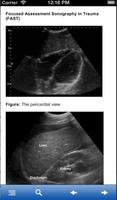

重点评估超声外伤